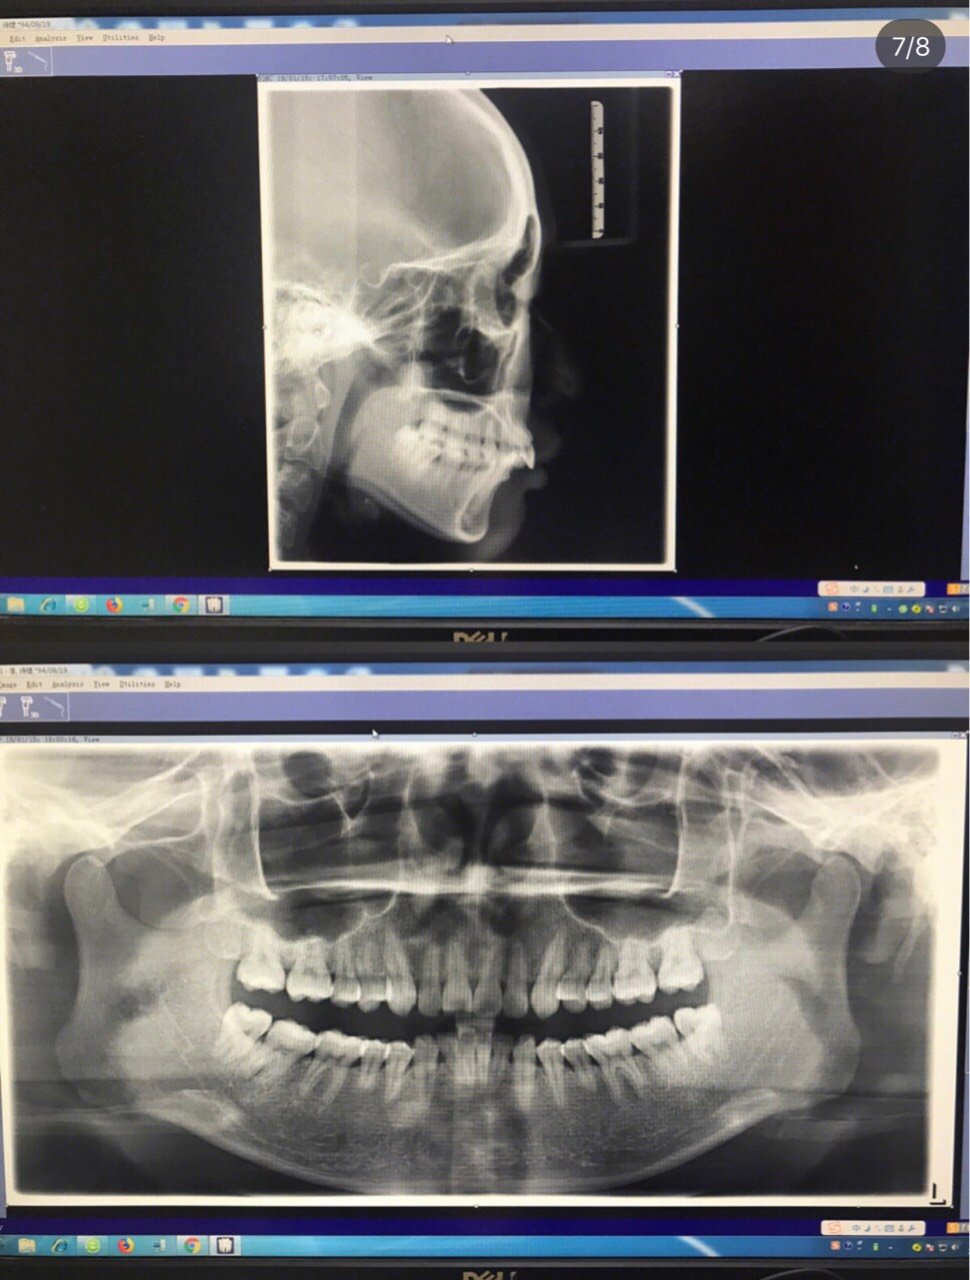

口扫出来的照片我是第一次见之前都是x光我对我牙齿的大概情况还是很了解的…然后在做了x光计算我🦷的密度

他们通过我牙齿的密度和精确的计算得出了我的最终方案和最终效果都特别满意 我差不多需要戴30副牙套15个月哈哈哈正好挤进